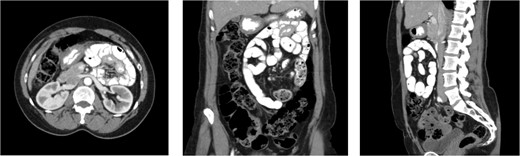

A 59-year-old female presented to our clinic with 10 years of vague episodic abdominal pain without prandial association. These episodes varied in severity, were self-limiting, and were not provoked by any identifiable factor. Her history was significant for asthma, GERD, and previous abdominal hysterectomy. The patient’s abdominal exam revealed only a Pfannenstiel scar but no tenderness, hernia, or palpable mass. The patient did not endorse any active symptoms in clinic. The patient underwent a CT scan of the abdomen and pelvis with IV and PO contrast which demonstrated small bowel loops in the right upper quadrant suspicious for herniation into a left paraduodenal space. Outpatient CT scan images can be found below (Fig. 5). The patient was scheduled for a diagnostic laparoscopy to evaluate for a paraduodenal hernia. Dense and extensive adhesive disease necessitated conversion to an upper midline laparotomy. The patient was found to have a left-sided paraduodenal hernia with the entire jejunum contained within Landzert’s fossa but without any signs of active obstruction. Additionally, the patient was found to have malrotation of the large bowel. After successful reduction of the non-obstructed small bowel, the mesenteric defect was then closed with a running silk stitch and the nearby proximal jejunum tacked over the repair. The malrotated large bowel was also placed in its correct anatomical position. The remainder of the procedure was uncomplicated with the patient recovering well.

CT images for Case 3, axial, coronal, and sagittal, respectively. The isolation of the contrast-filled small bowel can be appreciated in the right upper quadrant, representing bowel entrapped within the left paraduodenal hernia.